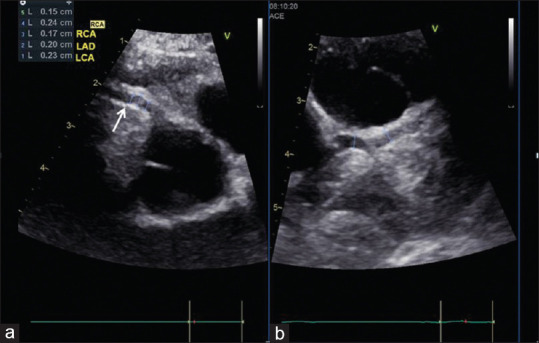

川崎病(Kawasaki disease, KD)是一种病因不明的儿童多器官和系统的全身性炎症性疾病。基本的病理改变是中小动脉,主要是冠状动脉的全血管炎。它现在是发达国家儿童获得性心脏病的主要原因,并导致心绞痛、心肌缺血/梗死的早期发展,甚至是成年早期的心源性猝死。虽然对KD没有明确的诊断测试,但准确的诊断取决于临床表现是否符合诊断标准。超声心动图是一种众所周知的无创工具,用于检测结构异常和评估心血管功能。据报道,它可以准确地检测早期和晚期心血管异常,包括血管周围亮度,缺乏锥形,扩张和冠状动脉动脉瘤形成以及二尖瓣/主动脉反流,心包积液和KD的心肌功能改变。对于KD形态不全及临床表现不符合诊断标准的患者,冠状动脉超声心动图异常可为KD的早期诊断提供帮助。长期定期超声心动图随访是KD患者首发冠状动脉异常的基础和必要研究。本文回顾并讨论了99篇研究KD超声心动图表现的文章。

Kawasaki disease (KD) is an etiology-unknown but with a generalized inflammatory disorder of multiple organs and systems in childhood. The basic pathologic changes are panvasculitis of the small and medium-sized arteries, mainly the coronary arteries. It is now the leading cause of acquired heart disease during childhood in developed countries and has led to the early development of angina pectoris, myocardial ischemia/infarction, and even sudden cardiac death in early adulthood. Although there is no definitive diagnostic test for KD, the accurate diagnosis is dependent on the clinical presentations to meet the diagnostic criteria. Echocardiography is a well-known noninvasive tool to detect structural abnormalities and evaluation of cardiovascular function. It has been reported to detect accurately the early and late cardiovascular abnormalities, including perivascular brightness, lack of tapering, dilatation, and aneurysmal formation of coronary arteries as well as the mitral/aortic regurgitation, pericardial effusion, and myocardial functional changes in KD. In cases of incomplete form of KD and patients whose clinical manifestations did not meet the diagnostic criteria, abnormal echocardiographic findings of coronary artery may provide the assistance for early diagnosis of KD. Long-term periodic echocardiographic follow-up is the basic and essential study for patients of KD with initial coronary arterial abnormalities. Ninety nine articles that studied echocardiographic findings of KD had been reviewed and will be discussed.